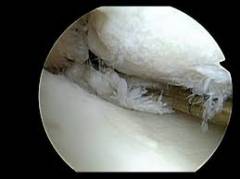

Артроскоп. Представляет собой разновидность эндоскопа, жесткую металлическую трубку толщиной 4-5 мм, в которой находится система линз. Это устройство позволяет получить изображение и вывести его на экран. К артроскопу подсоединяют световой кабель. -

Артроскопия коленного сустава: ход операции

- Первым в полость коленного сустава вводят артроскоп. Хирург делает надрез на коже скальпелем, а затем прокалывает подкожный жир и суставную капсулу при помощи троакара, и попадает в полость сустава.

- Обычно вместе с основным проколом делают еще два. Через них можно ввести инструменты и канюлю для промывания сустава. Всего в области коленного сустава существует 8 точек, в которых могут быть сделаны проколы во время артроскопии.

- Врач последовательно осматривает все внутрисуставные структуры. При необходимости может быть проведена артроскопическая операция.